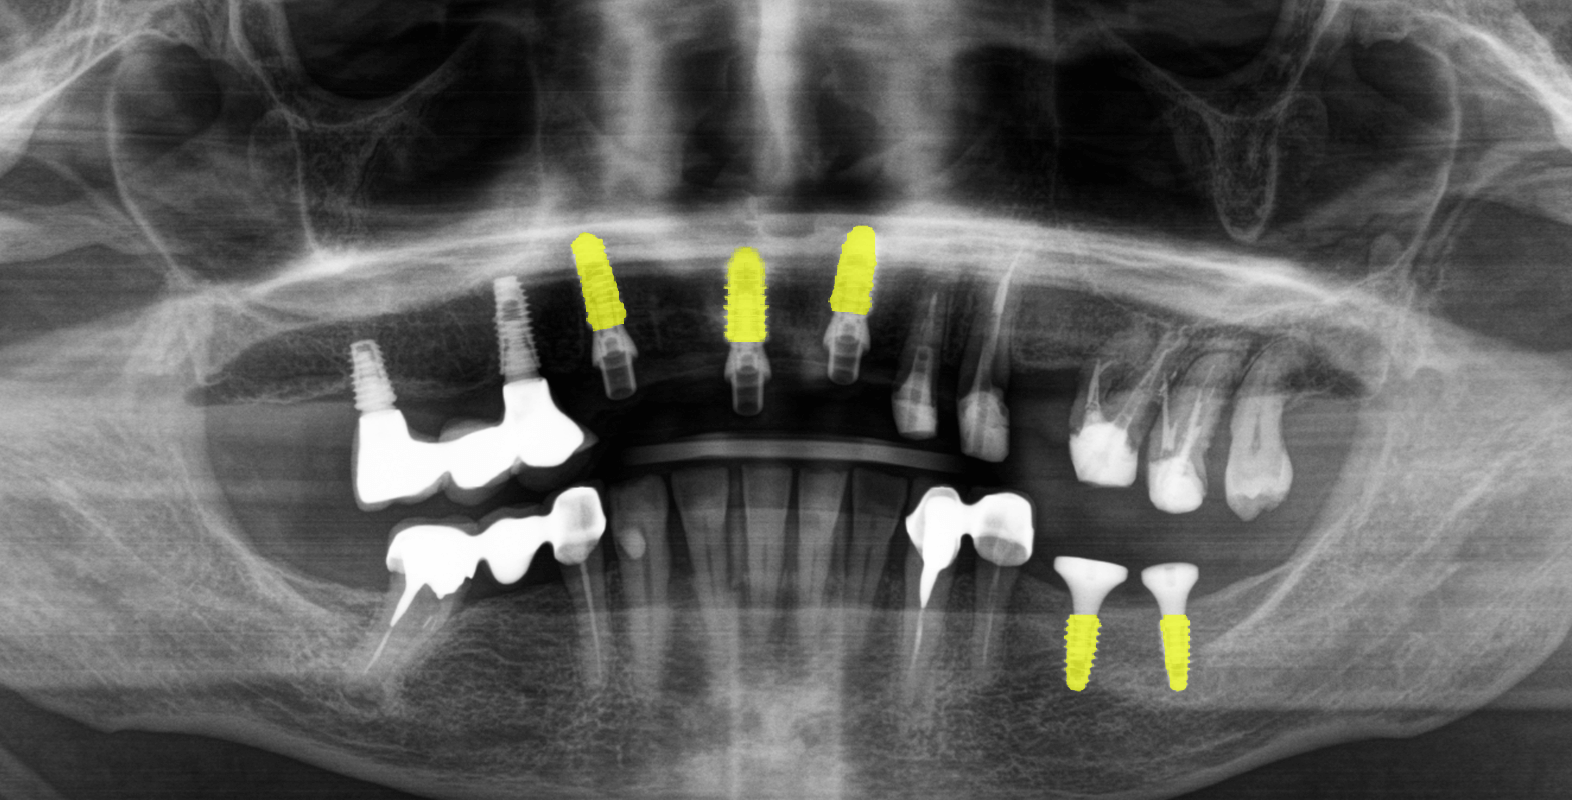

После анализа данных полученных путем компьютерной томографии и при очном осмотре было обнаружено:

- Установленный мостовидный протез на зубах 4.4 и 4.6 (зуб 4.5 отсутствует).

- Зубные коронки на зубах 3.3 и 3.4

- Зубы 3.6 и 3.7 отсутствуют.

- Имплантаты в области недостающих зубов 1.4, 1.6 и металлокерамический мостовидный протез на них с винтовой фиксацией.

- На зубах 1.3, 1.2, 2.1, 2.2, 2.3, 2.6 и 2.7 (2.4 и 2.5 отсутствуют) установлен металлокерамический мостовидный протез на родных зубах, который был подвижен и снимался вместе с вкладками.

- Зубы 1.2, 1.3 и 2.1 расколоты.

- Зуб 1.5 отсутствует.

- Кариозное поражение зуба 2.8

- Зубы 1.6 и 1.7 депульпированы.

- Катаральный гингивит на слизистой верхней челюсти (как следствие регулярного раздражения от подвижного металлокерамического протеза).

- Удаление зубов 1.2, 1.3, 2.1 с одномоментной имплантацией в области зубов 1.1, 1.3, 2.1, 3.5, 3.7 и аугментацией костной ткани.